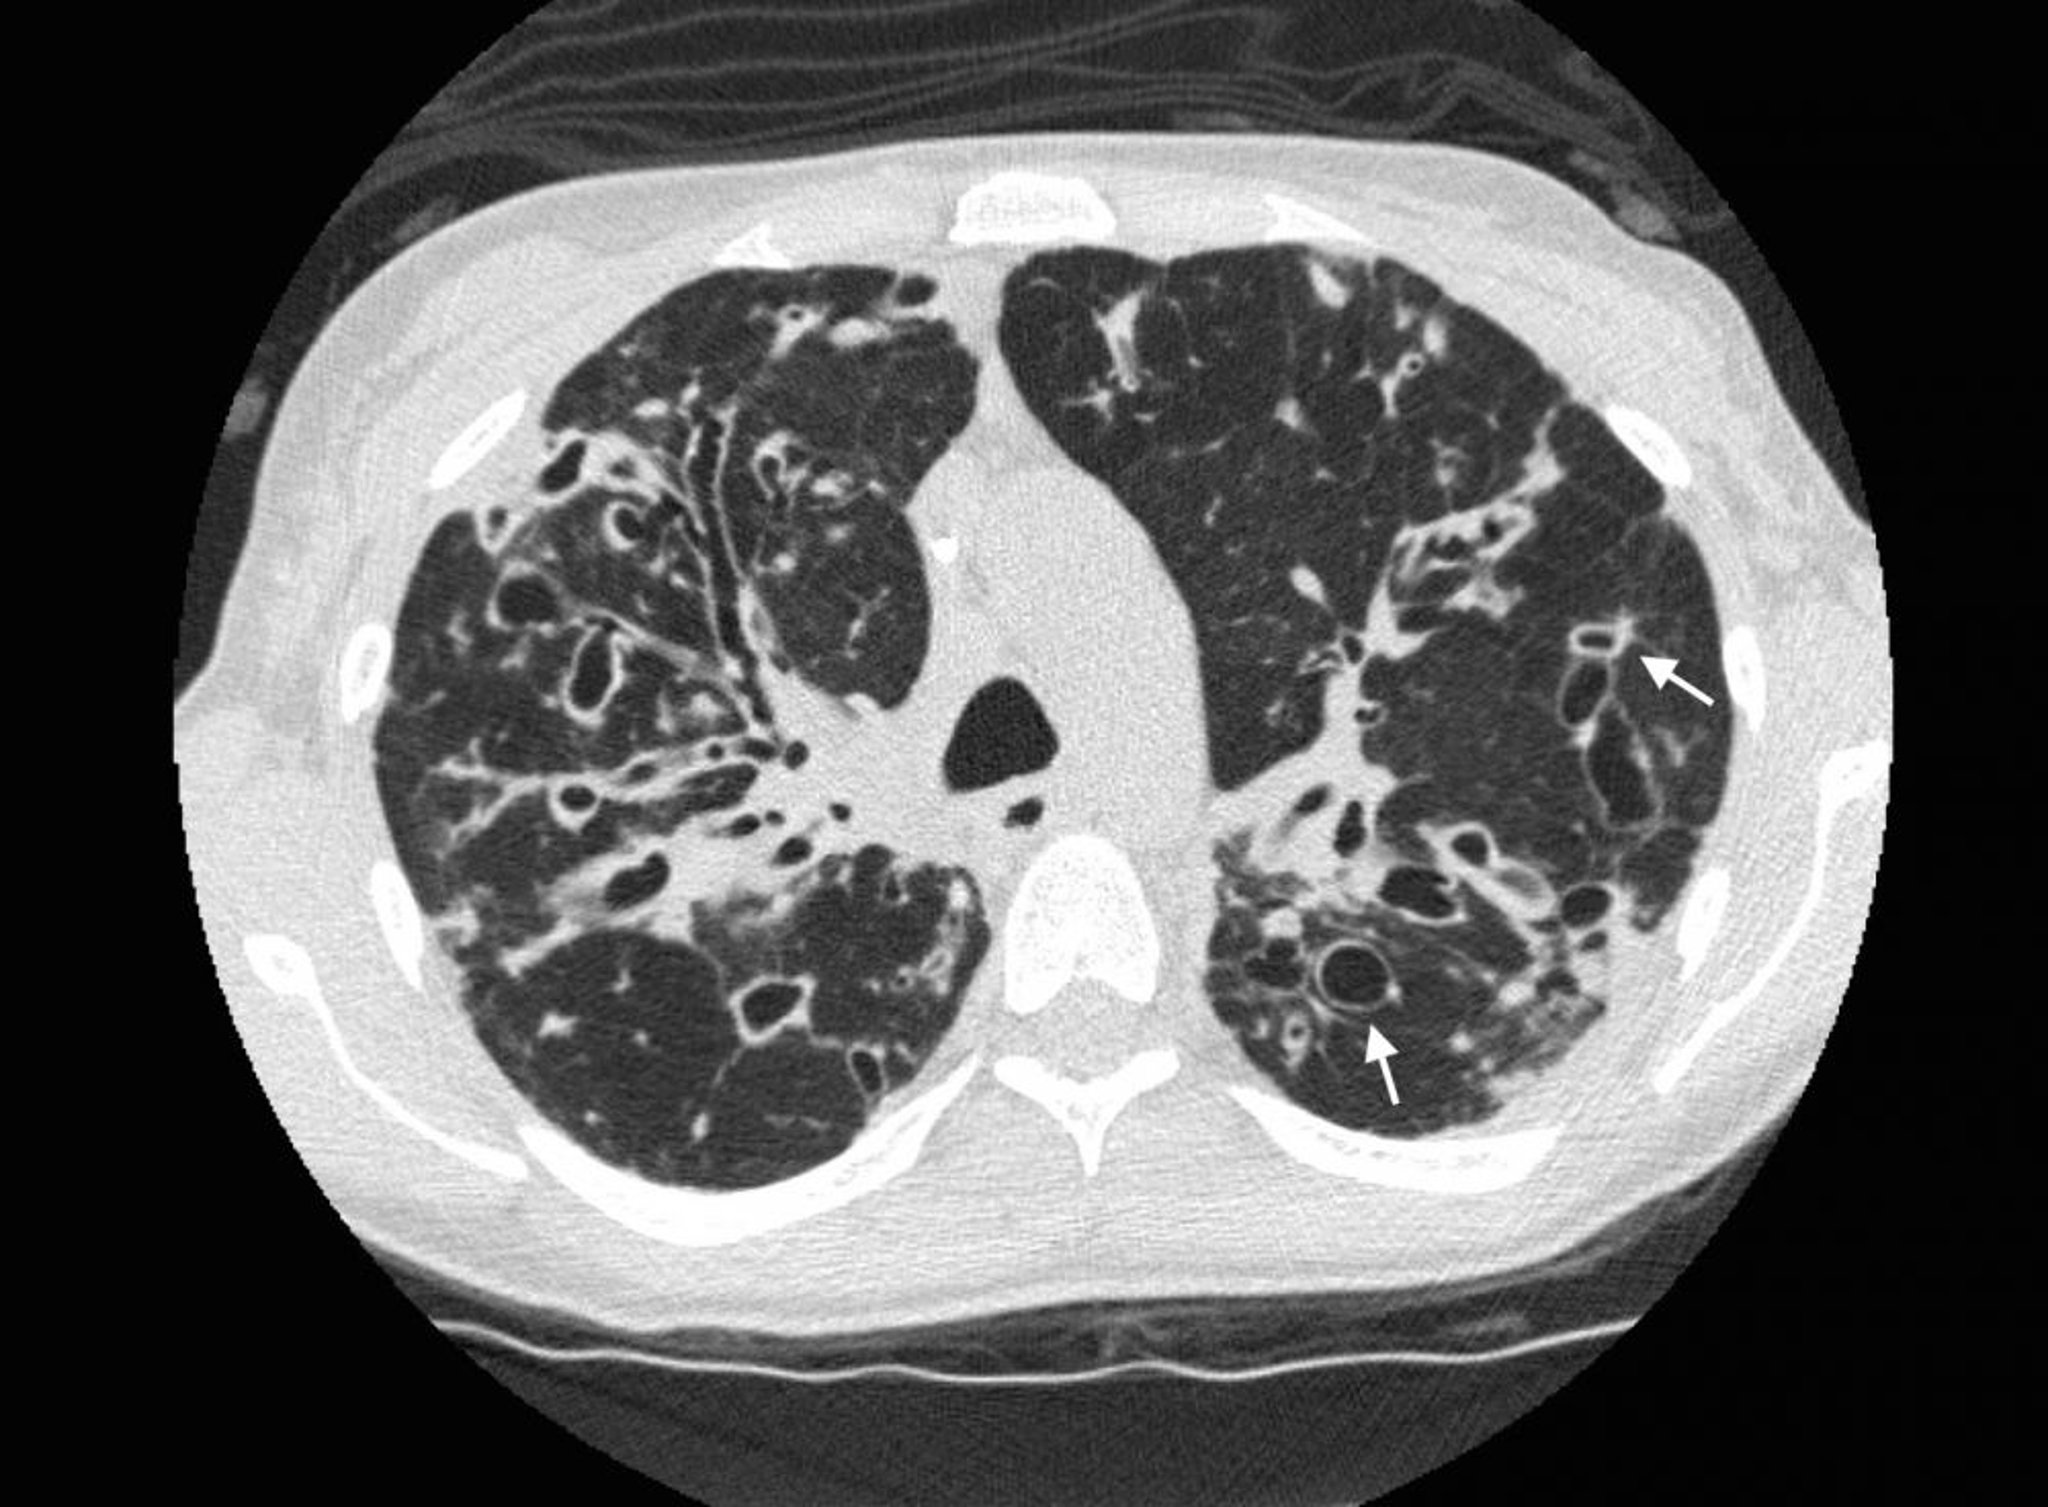

Bronquiectasia (tomografia computadorizada)

TC do tórax em um paciente com fibrose cística mostra bronquiectasias graves nos campos pulmonares superiores com dilatação das vias respiratórias e alterações císticas. As setas mostram o sinal de anel de sinete, no qual uma via respiratória dilatada (o anel) é adjacente a uma artéria menor (a parte superior do anel). Normalmente, as vias respiratórias são do mesmo tamanho ou menores que as artérias adjacentes.

Photo courtesy of Başak Çoruh, MD.